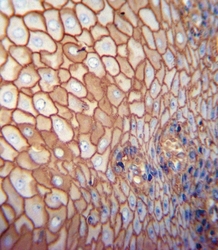

Supportive validation

- Submitted by

- Arigo (provider)

- Main image

- Experimental details

- Immunohistochemistry: human esophagus carcinoma stained with ARG54697 anti-CD44 antibody.